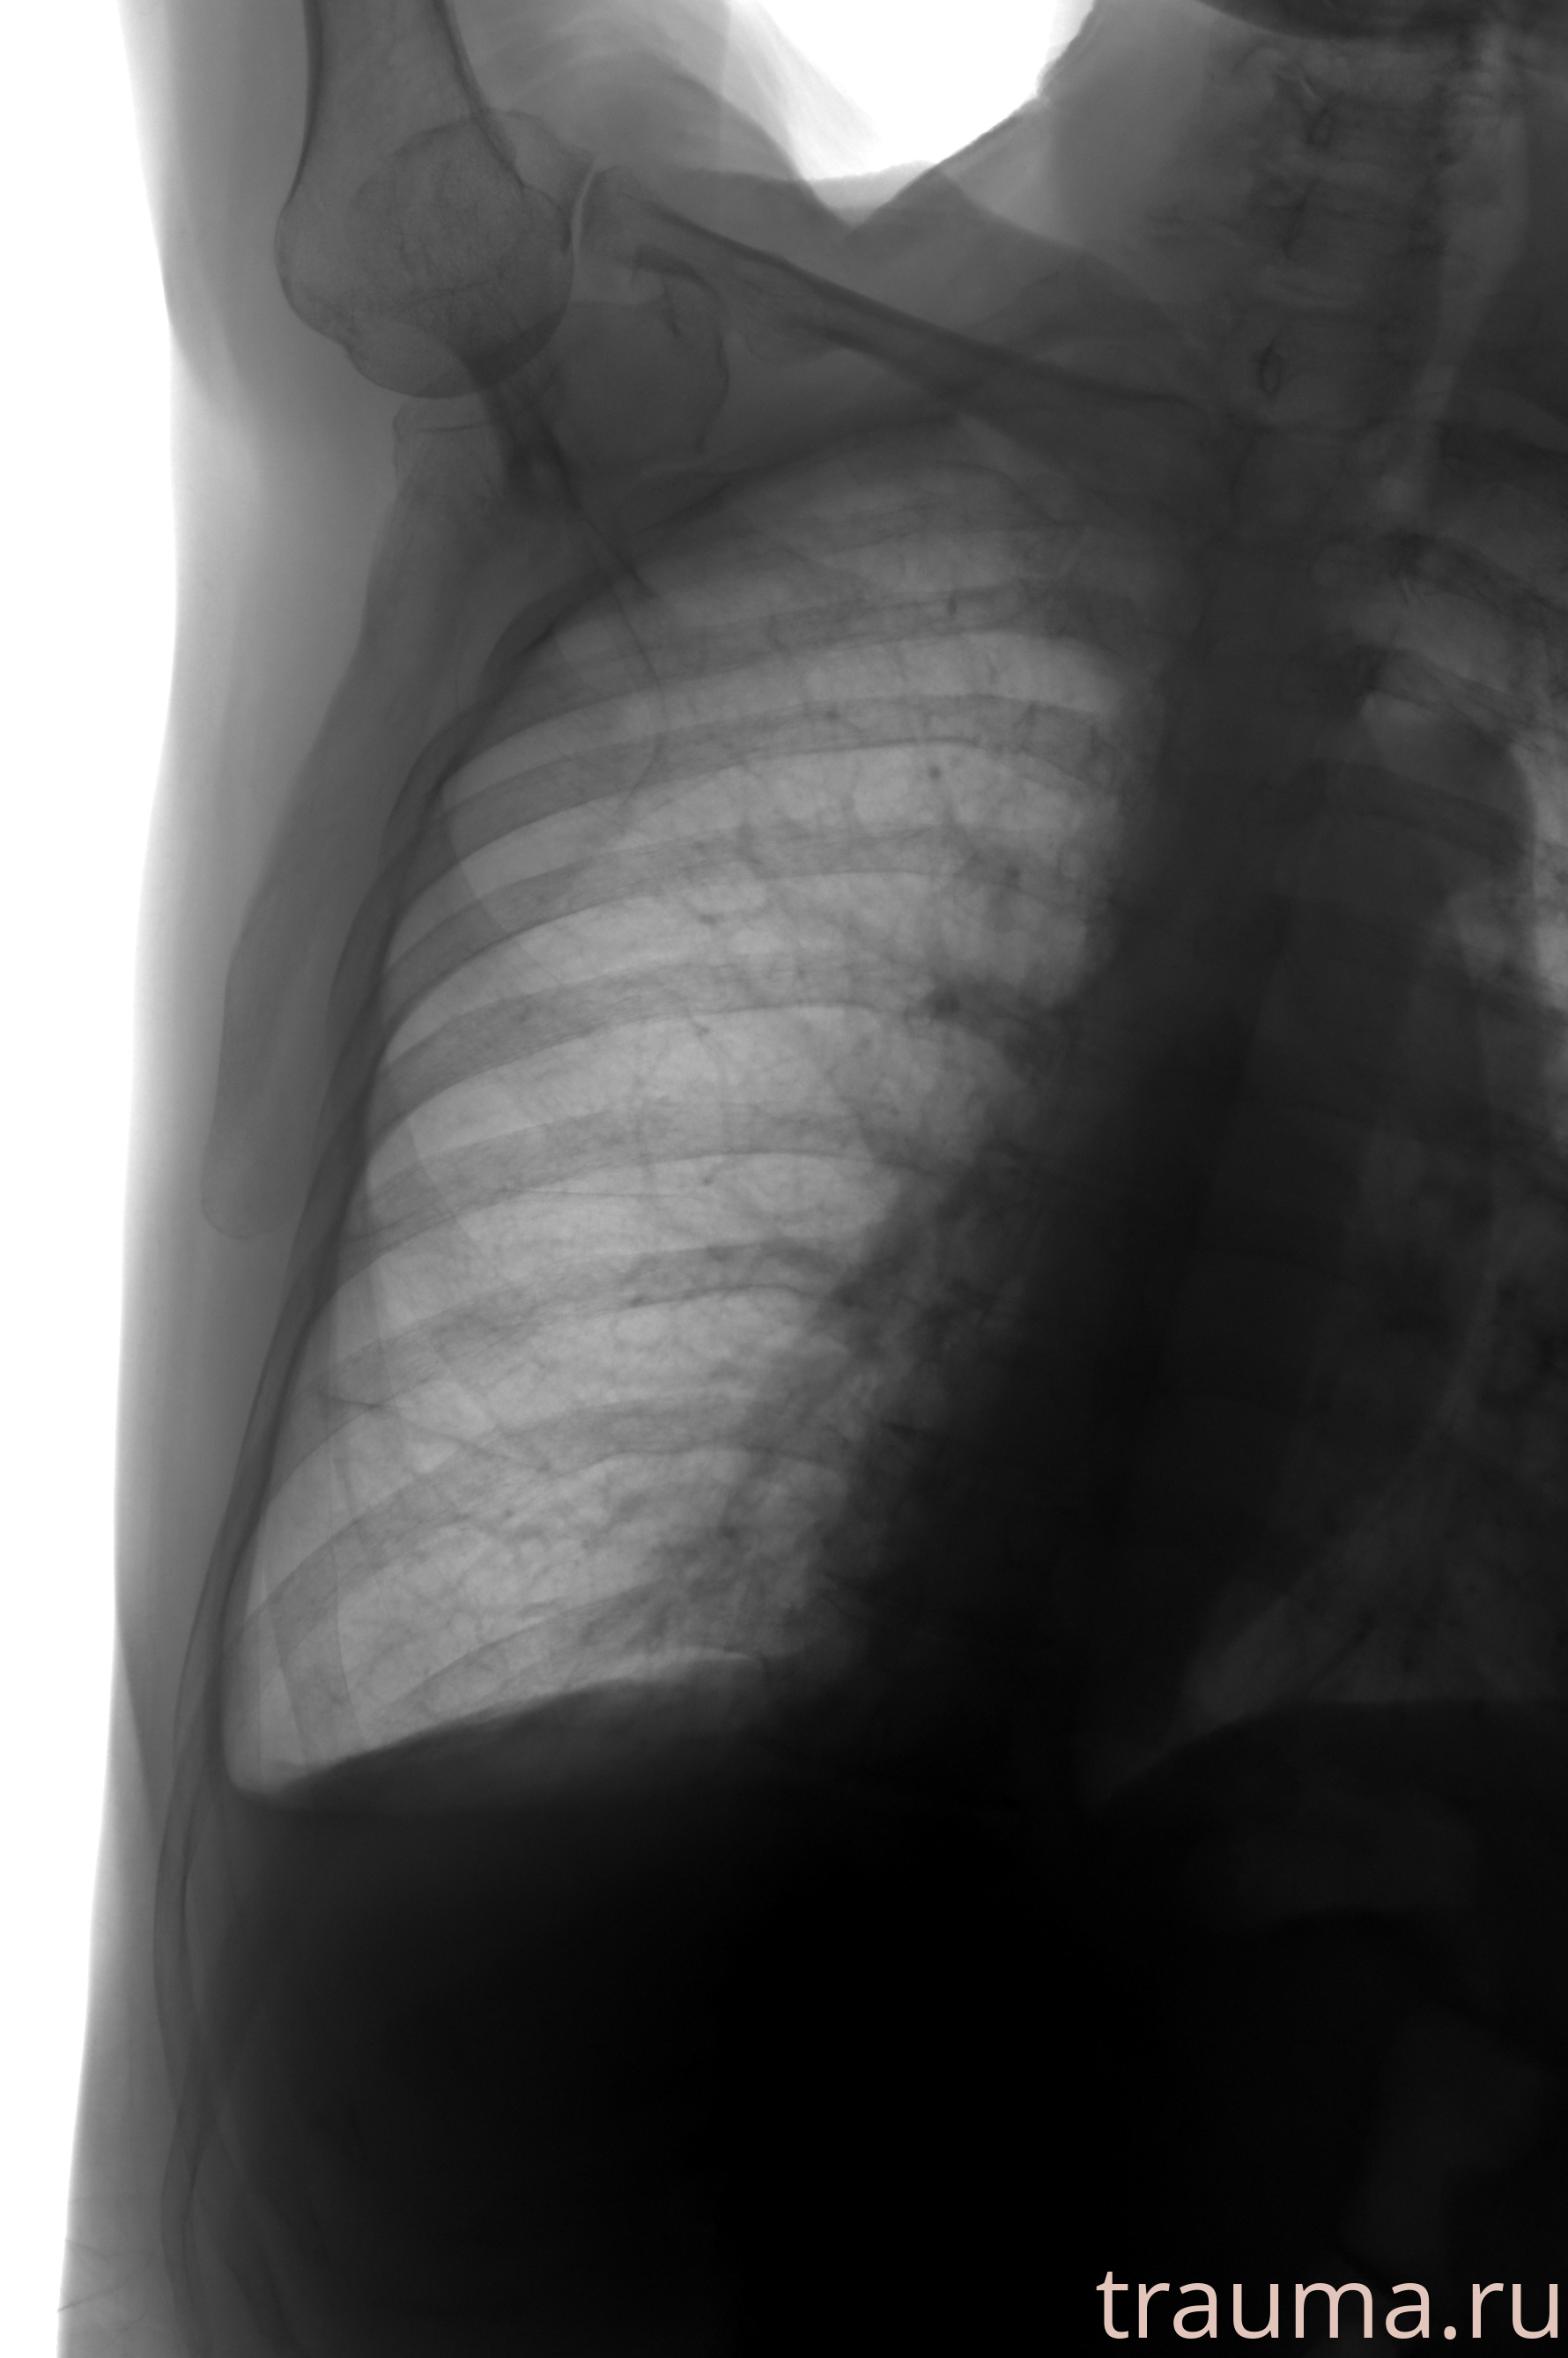

Рентгенограммы

Натуживание 26.12.2025 21:16:34

Рентген на дому: по вашему адресу приезжает врач-рентгенолог, травматолог-ортопед с мобильным рентгеновским аппаратом, проводит диагностику травмы или заболевания, делает необходимые рентгенограммы, дает рекомендации по дальнейшему лечению. Получить качественные снимки в домашних условиях возможно благодаря уникальной методике, разработанной МосРентген Центром для института  Склифосовского